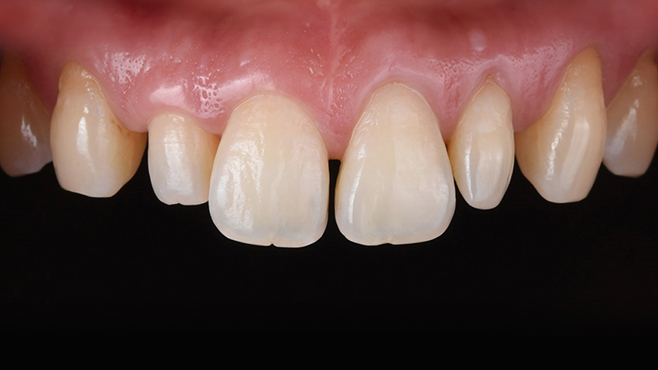

맞는 건 괜찮은데… 충치는 못 참겠습니다|20대 격투기 선수 치과 방문기